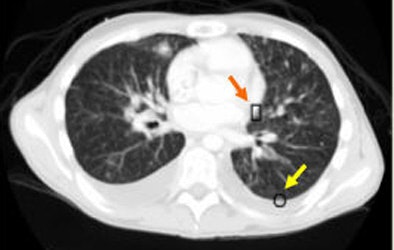

| An example of successful nodule classification. The circle encloses a true wall nodule. The rectangle surrounds a very similar wall object that is in fact a false positive erroneously detected by the group's previous CAD system. The current hybrid FP reduction approach recognizes and removes this false-positive finding. |

| An example of successful nodule classification. Above, bright well-formed true nodules marked inside circles. Below, very similar non-nodule objects marked inside rectangles. The hybrid FP reduction stage accurately categorizes these objects as false positives. |